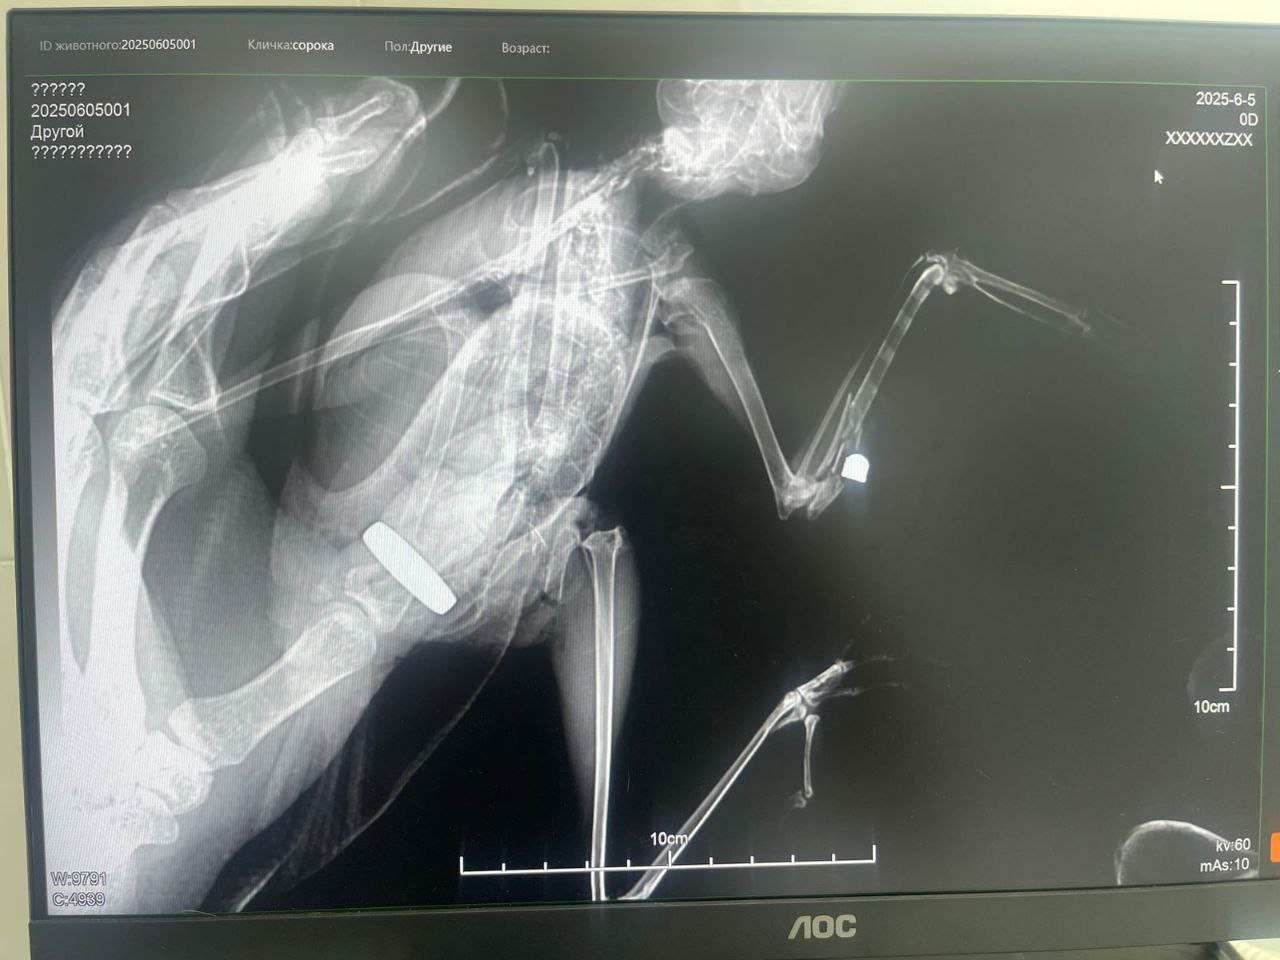

Потом женщина поняла, что птенца надо везти в ветеринарную клинику. Там рентгеновский снимок показал в теле птицы маленькую пулю, вероятней всего, от пневматического оружия.

Что касается осиротевшего птенца, то, помимо пулевого ранения, у него ещё травмирована лапка, а также необходимо разрабатывать крылья, иначе птенец погибнет от пневмонии.

«Птенца пытаемся выходить. Выяснили, что только в Краснодаре есть врач-хирург, который готов его взять. Если птенец доживёт, в выходные поедем извлекать пулю. После этого мы его либо отдадим в заповедник, а если его не возьмут, оставим себе», — добавила женщина.